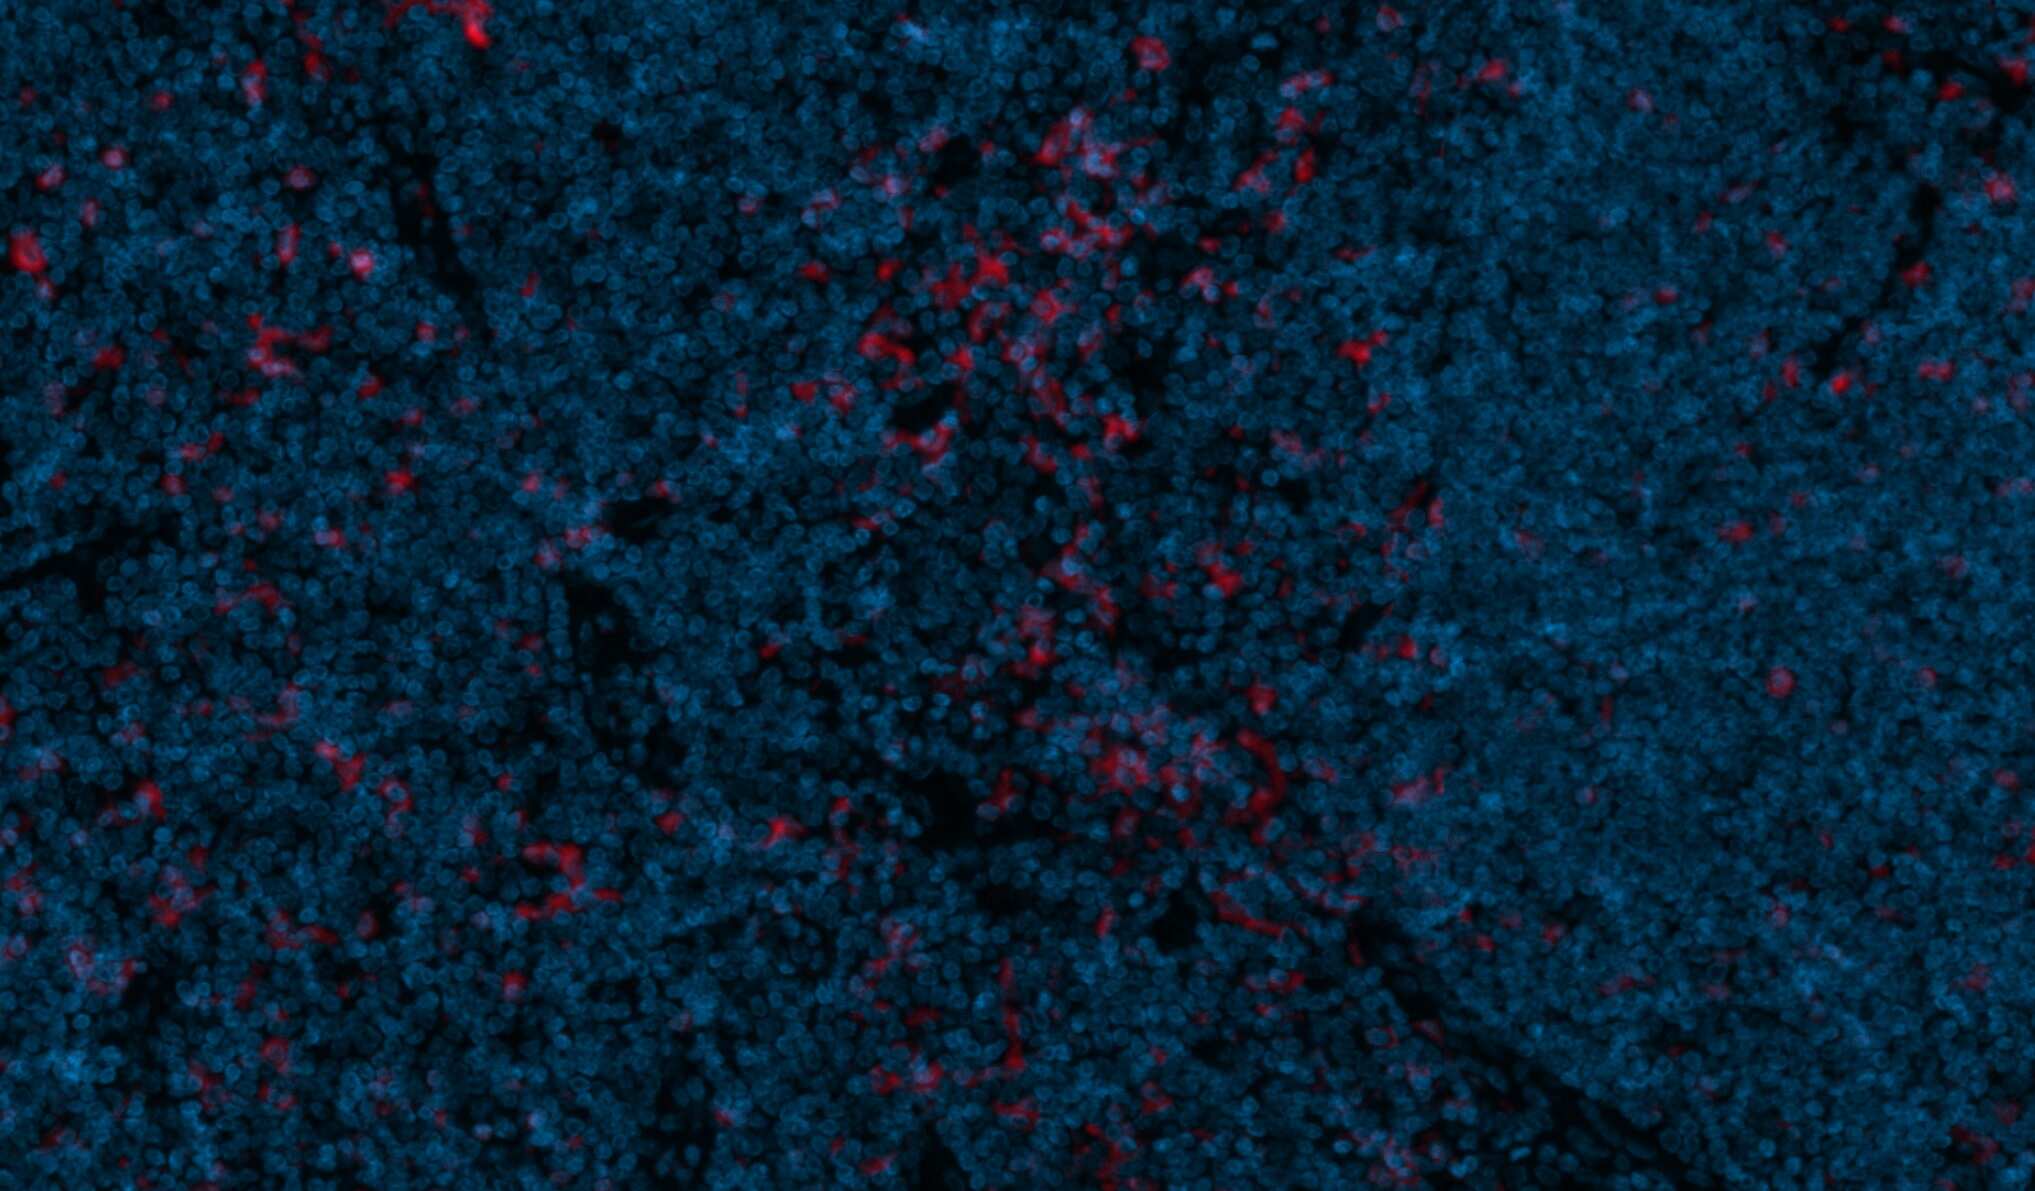

Immunohistochemistry-Paraffin: CD11c Antibody (ITGAX/1243) [NBP2-44599] -

Immunohistochemistry-Paraffin: CD11c Antibody (ITGAX/1243) [NBP2-44599] - CD11c was stained in human FFPE tonsil tissue. HIER antigen retrieval was performed at pH 9 for 20min. Concentration used: 1:50. AF750 conjugated version of the antibody was used (Catalog # NBP2-54432AF750). Image from a verified customer review.